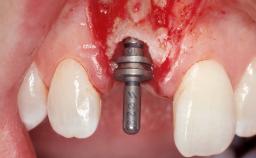

Immediate Flapless Placement of an Implant in a Maxillary Right Lateral Incisor Site

This 43-year-old male patient, a non-smoker, came to our practice because of a fracture of tooth 12 caused by a bicycle accident. Due to the combined para- and infrabony crown and root fracture, tooth extraction, and subsequent implant placement were suggested to the patient as the therapy of choice. The patient had high esthetic expectations with regard to the treatment outcome and asked for an immediate fixed provisional restoration. His individual esthetic risk profile summed up to a medium esthetic risk.

Type of Implants Two-Piece

Placement Protocol Immediate implant placement

Loading Protocol Immediate

Retention Screw-retained Screw-retained